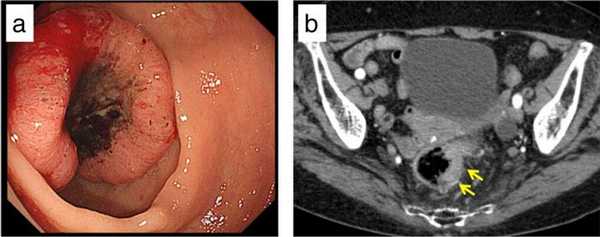

a - С помощью предоперационной колоноскопии выявлена опухоль, локализованная в верхней части прямой кишки.

b - Проведена КТ с контрастированием, с помощью которой выявлено утолщение прямой кишки.